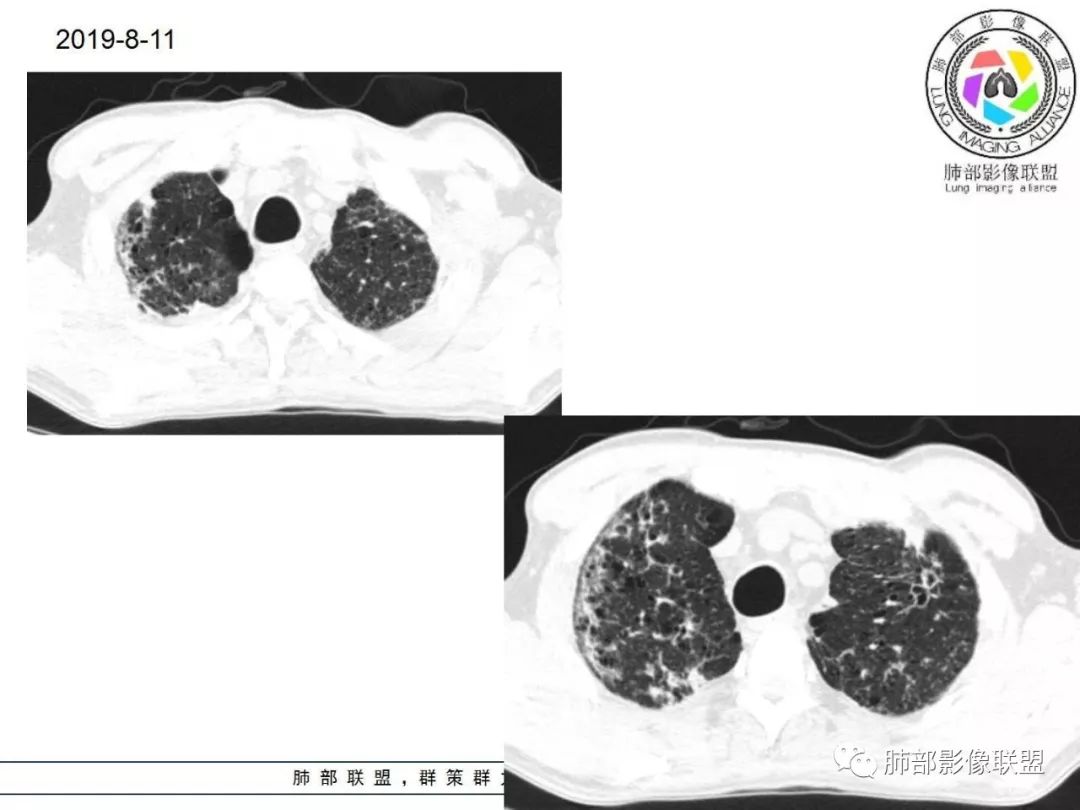

胸部CT:两肺弥漫病灶,磨玻璃影,少许实变,部分累及胸膜,磨玻璃区可见囊?少许胸腔积液,两肺可见结节,支气管血管束增粗,小叶间隔增厚,支气管走形有扭曲扩张,可见纤维化。气肿、大泡。考虑:感染性病变,PCP?查下HIV,CD4,G等。鉴别结核、结缔组织病肺浸润。

两肺肺气肿,弥漫GGO+实变影,局部伴牵拉性支扩,分布无规律。左侧胸膜明显增厚。双肺门淋巴结钙化。

中年男性,亚急性起病,发热,咳嗽,黄痰,具体治疗不详,CRP增高,余感染指标及特异性指标不详,基础疾病不详,胸部CT提示双肺散在索条影,右肺为重,胸膜下及中央间质分布为主,磨玻璃影,牵拉性支扩,实变,有囊,LIP合并感染。

胸部CT:两肺弥漫病灶,中央间质分布为主,部分位于胸膜及叶间裂旁,磨玻璃影,斑片影,部分实性结节,肺气囊,支气管血管束增粗,小叶间隔增厚,叶间裂不均匀增厚,支气管走形有扭曲扩张,可见纤维化、气肿、大泡。考虑:LIP加MALT。鉴别PLCH、PCP、结核、结缔组织病肺浸润。

双肺弥漫性病变,多发磨玻璃密度及小叶间隔增厚,大部分沿支气管血管束分布,伴支气管轻度扩张,以午后及晚上发热为主,考虑感染性病变,间质性结核可能大,另双肺多发肺气囊,LIP待排

中老年男性,双肺弥漫性病变,呈网状、斑片及大片状,实变影及磨玻璃影相间,部分病灶区支气管扩张,并见多发小囊状或蜂窝状透亮影,中央间质增厚,气管前单发小淋巴结。考虑淋巴细胞增生性病变?粘膜相关性淋巴瘤(MALT)或淋巴细胞间质性肺炎(LIP)?鉴别机化性肺炎(OP)及结核(TB)。

两肺弥漫病灶,中央间质分布为主,部分位于胸膜及叶间裂旁,磨玻璃影,斑片影,部分实性结节,肺气囊,支气管血管束增粗,小叶间隔增厚,叶间裂不均匀增厚。考虑:间质性肺病,LIP,鉴别OP

双肺肺气肿背景,双肺弥漫分布磨玻璃及实变密度,病灶沿血管支气管束及胸膜下分布为主,部分病灶以平直收缩为主,局部支气管稍扩张,管壁增厚,小叶间隔增厚,结合临床病史,考虑炎性病灶,感染伴病灶机化?结核?NTM?

中老年男性,发热1月余,双肺弥漫性病变,多发网格、结节、斑片状实变影及磨玻璃影,胸膜下及中轴间质都受累,支气管血管束增粗、变形,支气管扩张,叶间裂及小叶间隔增厚,整体间质性改变明显,考虑结核?OP、LIP?进一步除外PCP、肿瘤、结节病等。

2. 肺气肿背景(小叶中心性肺气肿);双肺多发病灶整体沿血管支气管束及胸膜下分布,以上叶及下叶背段分布为主,有实变及GGO,边界清楚,有树芽,小叶间隔及中央间质增厚,叶间裂见到多发结节,部分支气管不规则牵拉扩张,提示病灶纤维化明显,结合临床病史,考虑病灶为间质性感染,肺门及纵隔内有钙化淋巴结,小叶间隔结节,考虑淋巴道增值性疾病可能,综合常规要怀疑间质性肺结核。